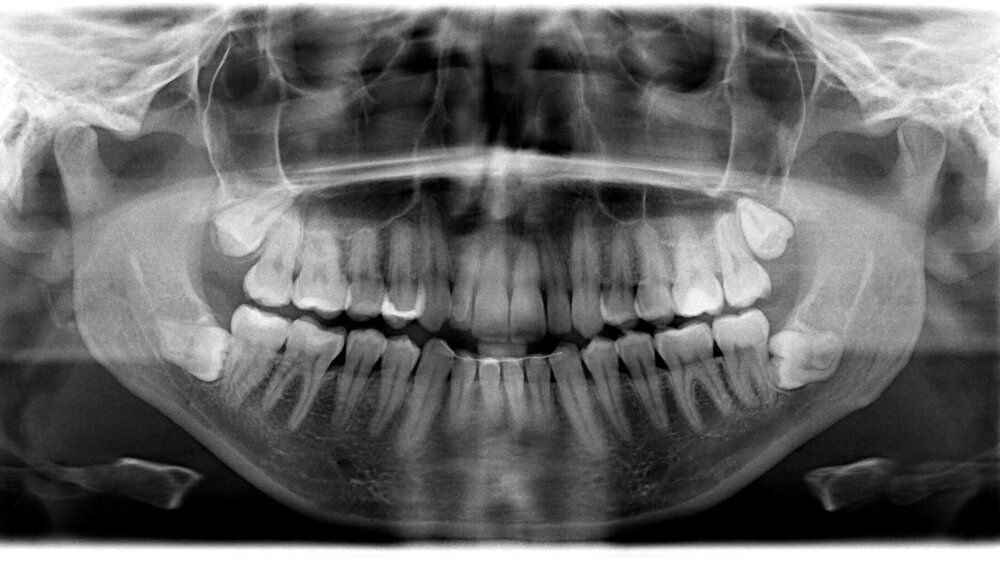

Ein Großteil der Menschen hat mindestens einen Weisheitszahn angelegt. Sind dritte Molaren verlagert, werden sie üblicherweise im Jugend- oder frühen Erwachsenenalter entfernt. Die Entfernung impaktierter oder retinierter Weisheitszähne erfolgt durch Bildung eines Mukoperiostlappens sowie einer Osteotomie des darüber liegenden Knochens mit Hilfe einer Knochenfräse unter gleichzeitiger Spülung.

Um zu prüfen, ob die Temperatur der Spülung einen positiven Effekt auf den postoperativen Verlauf hat, haben Forschende aus der Türkei insgesamt 48 Patienten (28 Frauen, 20 Männer) asymptomatische dritte Molaren im Unterkiefer unter Spülung mit unterschiedlich kalten Kochsalzlösungen entfernt. Die Forschenden verwendeten ein split-mouth Design und entfernten in zeitlichem Abstand zueinander erst einen und danach den zweiten Unterkiefermolaren unter Verwendung von Kochsalzlösung. (4 °C, 10 °C oder 25 °C).